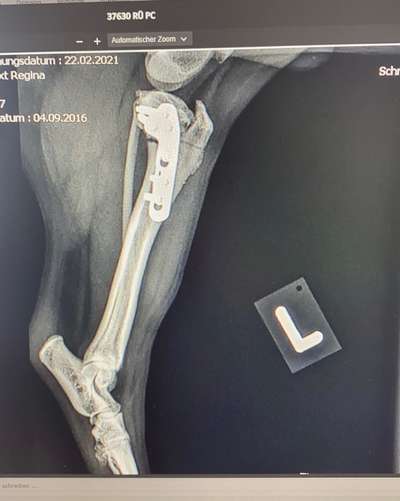

Bei meiner Bordeaux Dogge (Kreuzbandriss und Bruch im Schienbein ) wurde ein Käfig und Platten eingesetzt. Es war auch gut verheilt. Wie oben schon gesagt, nicht zu viel Toben und Springen wurde uns in der Klinik gleich gesagt.

Mittlerweile hat sich auch rausgestellt, dass bei der OP scheinbar die Fibia (das Wadenbein) durchgeknackst ist, was uns niemand mitgeteilt hat, als wir ihn abgeholt haben. Insgesamt eine sehr sehr unschöne Nummer alles, auch wenn der Knochen wohl von selbst wieder zusammenwächst. Aber es erklärt die Schwellung und die Schmerzen, die die arme Töle nach wie vor hat. 🥲 Status quo ist, dass die Nähte heute immerhin raus konnten, wir ihn aber bis auf Weiteres bei den 3 x 5-10 min täglich belassen. Schmerzmittel kriegt er weiterhin, schont leider auch noch sehr das Beinchen und fängt leider nach den letzten 12 Tagen schon an zu Zittern, wenn wir (so wie heute früh) auch nur eine Praxis betreten.